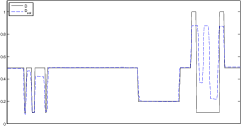

The data (see Figures 1 and 2) was generated in the diffusion model (1.2) using self-written (linear-basis) finite element code in MATLAB. For both examples, we took and used a uniform boundary condition . The simulated data were generated on a -grid and then down-sampled (by averaging) to to avoid inverse crime. After that, Gaussian noise with different intensities (standard deviations of and of the average signal value ) was added to the data.

Reconstruction results and error profiles at different noise levels can be seen in Figures 3 and 4. In both examples, the noise-free reconstructions are very accurate and contain mostly smoothing error. In the low-noise reconstructions, due to the fact that more regularization is necessary, some of the parameter variation is underestimated. In the high-noise examples, most detail in is lost since a lot of regularization is required to get reasonable results. The fine detail in can, however, still be recovered very accurately in both examples.